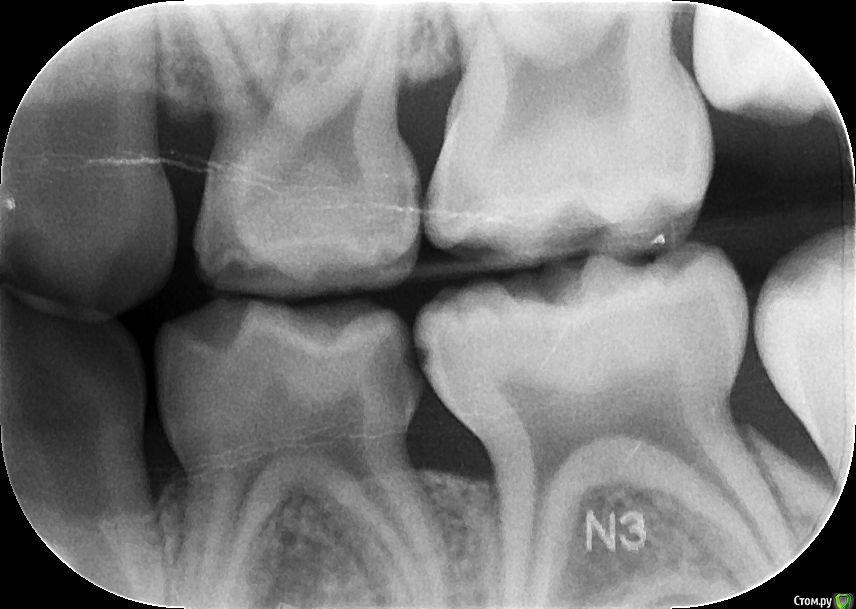

Elena Bundren Опубликовано 27 июня, 2018 Поделиться Опубликовано 27 июня, 2018 Здравствуйте!Пришли с 5-летним ребенком к стоматологу. Он обнаружил 12 кариесов, сказал, на несколько зубов надо ставить серебренные коронки.Моляр справа внизу подлежит удалению, так как под ним инфекция.И все это хорошо бы сделать под общей анестезией за один раз.Вопросы уважаемым докторам, сколько, по-вашему, зубов реально подлежит лечению, и есть и возможность, на ваш взгялд, сохранить моляр, если да, то какое нужно лечение.Также, каково ваше мнение об общей анестезии для ребенка 5 лет. Ссылка на комментарий

St. Опубликовано 27 июня, 2018 Поделиться Опубликовано 27 июня, 2018 Добрый день. Зубы действительно в очень плохом состоянии и практически на всех между зубами есть кариес.Металлические коронки у детей это хорошо, они позволяют надежно провести лечение сильно разрушенных зубов и не опасаться сколов и вторичного кариеса. Ссылка на комментарий